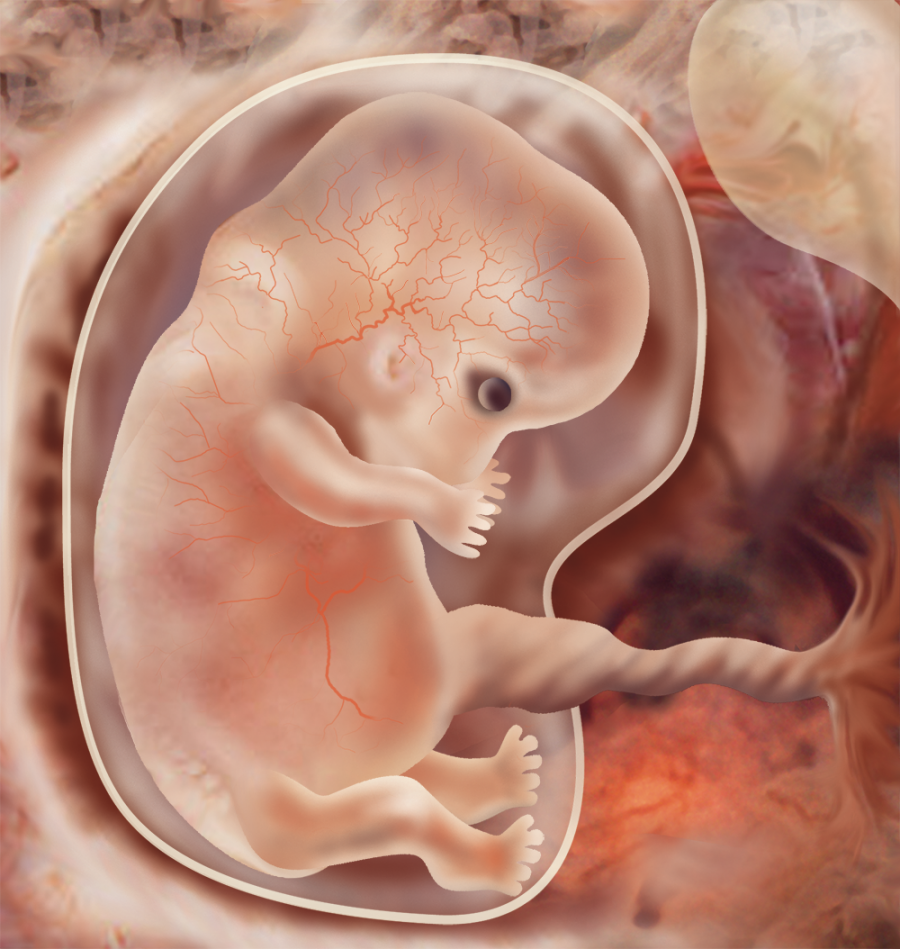

Эмбриональный период: Развитие эмбриона от зачатия до рождения